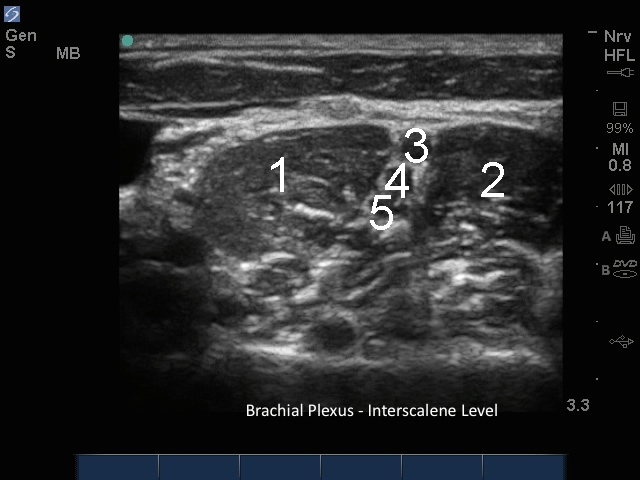

M-Turbo: Brachial Plexus Interscalene Level 3

1. ASM

2. MSM

3. C5

4. C6

5. C7